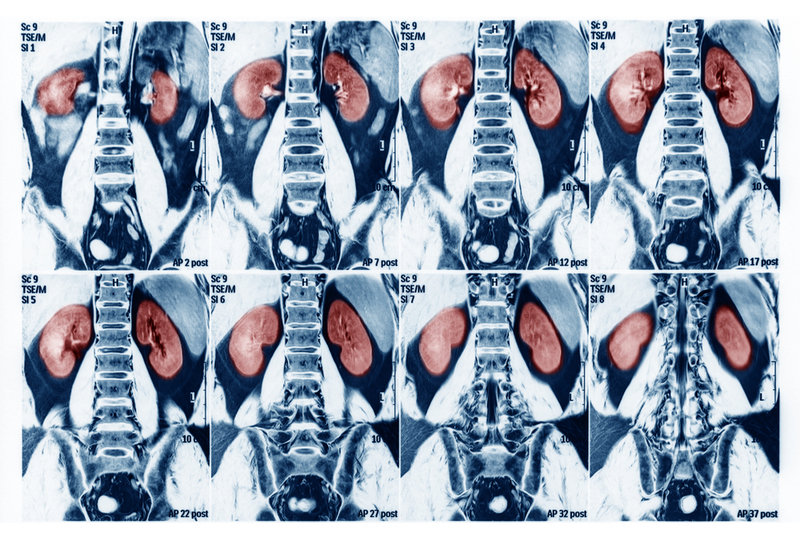

Acute kidney injury, an often fatal condition without a specific treatment, causes a build-up of waste products in the blood and an imbalance of fluids throughout the body. "Acute kidney injury, even with complete renal recovery, is associated with an increased risk of dementia," said Jessica Kendrick from the University of Colorado in the US.

Acute kidney injury, that affects 30-40 per cent of all hospitalised adults in the low-income countries, is an abrupt decline in kidney function. It often arises after major surgeries or severe infections and is associated with long-term health problems including the development of chronic kidney disease and cardiovascular disease.